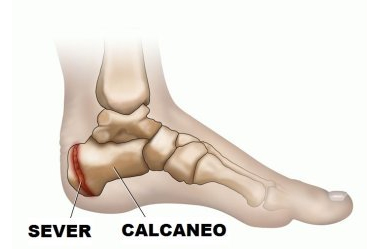

La enfermedad de Sever corresponde a un grupo de alteraciones del esqueleto en desarrollo conocidas como osteocondrosis. Se trata de un cuadro doloroso del talón, que afecta a niños(as) entre los 9 y 13 años de edad, en especial durante o después de realizar actividad deportiva.

La osteocondritis de Sever es una alteración típica de las llamadas “del crecimiento”. Los dolores son el resultado de un crecimiento rápido al tiempo que se tiene una actividad deportiva muy intensa. Los deportes que implican pisotones y saltos, como el fútbol, el tenis, el atletismo, la marcha, la gimnasia o incluso la danza son los más propensos a generar la patología.